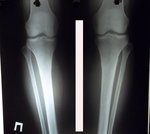

Дата операции 14.04.2016г.

Исходник - 46 лет.

рентген до операции